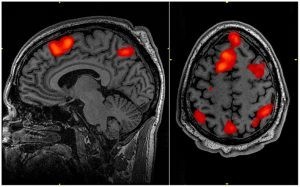

A doença não tem cura e causa a morte das células do cérebro - (Foto: John Graner/Walter Reed National Military Medical Center)

Câmara dos Deputados Há 3 anos

Sancionada criação do Dia Nacional da Doença de Huntington

John Graner/Walter Reed National Military Medical Center A doença não tem cura e causa a morte das células do cérebro O presidente da República, ...